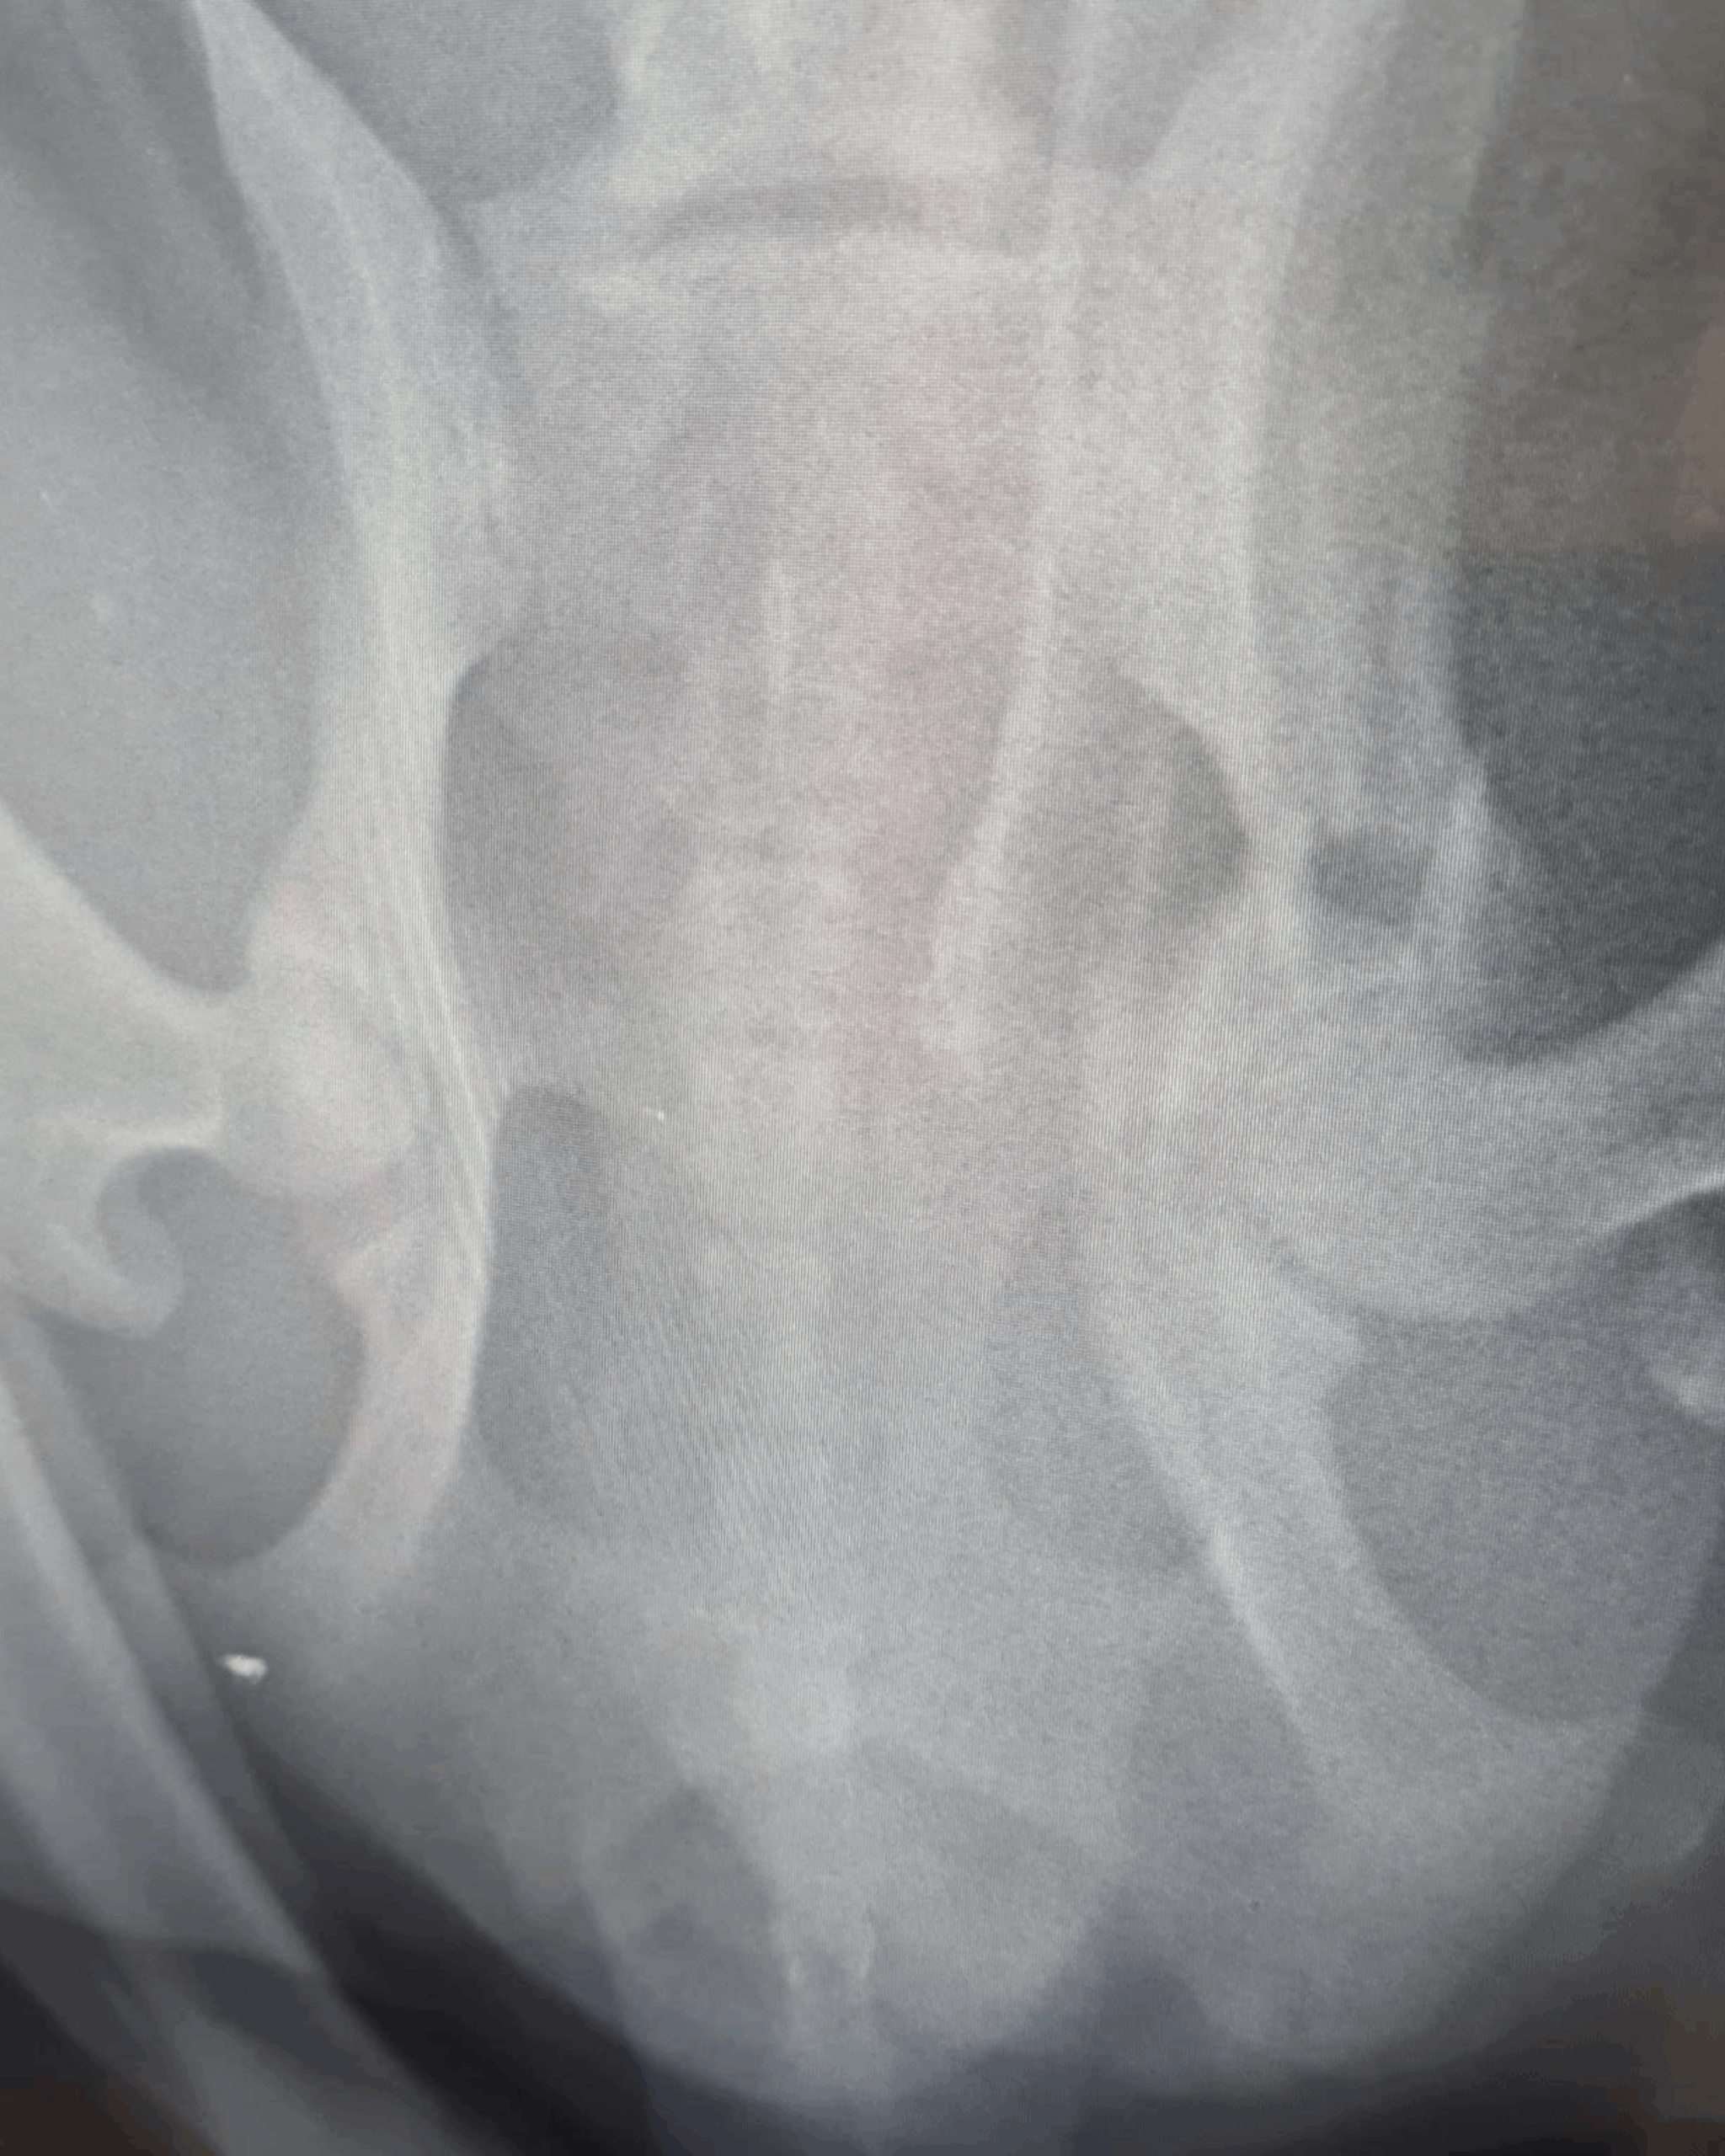

Dodatkowo zdiagnozowano u niego babeszjozę – chorobę odkleszczową. Kleks miał złamania obu kończyn: przedniej lewej (kość łokciowa i promieniowa) oraz tylnej prawej (panewka stawu biodrowego). Początkowo musiał zostać ustabilizowany, zanim możliwe były operacje. 3 marca poskładano jego łapę, a 11 marca zoperowano miednicę. Pogruchotaną kość udało się złożyć, a głowę kości biodrowej częściowo usunięto – pęknięcie panewki mogłoby powodować dalsze problemy i konieczność kolejnych zabiegów.